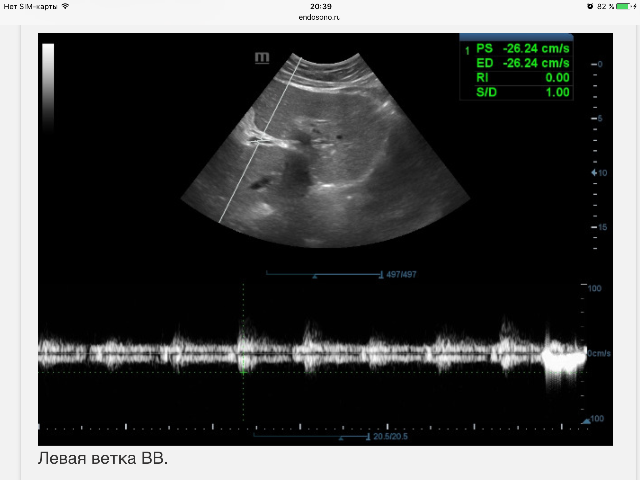

А на картинке "Левая ветка ВВ"

кровоток одновременно в двух направлениях. Иногда он бывает таким, если допплеровский угол равен 90°.